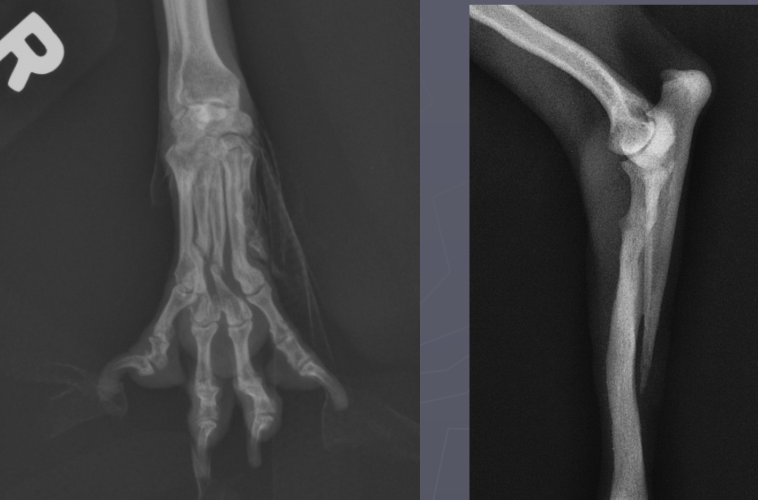

What is shown in these radiographs?

erosive polyarthritis

non-erosive polyarthritis

joint-associated neoplasia